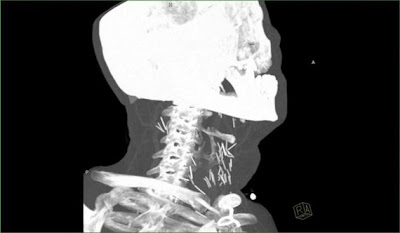

Un ragazzo americano, consumatore abituale di droghe, ha un terribile dolore al collo e così si rivolge al suo medico; il quale gli fa dell lastre per vedere se c'è qualcosa che non va.... immaginate la sorpresa nel vedere che ci sono almeno una decina di chiodi conficcati nel collo!!!